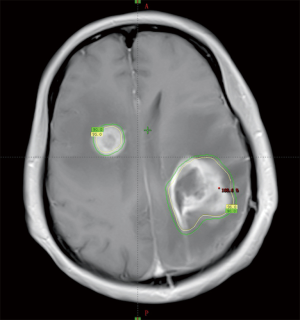

A 51-year-old female patient presented with right-limb paralysis as onset. In June 2016, T1-enhanced magnetic resonance imaging (MRI) of the head showed an abnormally enhanced occupancy signal in the left parietal and right frontal areas. Moreover, in July 2016, the left parietal lesion was surgically removed and pathologically confirmed as GBM (World Health Organization, grade IV). A postsurgery Gd-enhanced T1-weighted MRI was performed, as shown in Figure 1. She then received a postoperative 6-week intensity-modulated radiation therapy (IMRT) during which temozolomide [75 mg/m2, once daily (qd)] chemotherapy was synchronized. The IMRT was arranged as follows. In the first phase, radiation was given 2 cm outside the range of fluid attenuated inversion recovery (FLAIR) abnormal signal at an exposure extent of 40 Gy/20 f. This was followed by an MRI re-examination with a simultaneous integrated boost technique conducted for a right frontal lesion in the range where the T1 was enhanced. Moreover, the left parietal lesions within the surgical cavity were irradiated at 24 Gy/10 f, with simultaneous radiation to the area with FLAIR abnormal signal at 18 Gy/10 f. The dose distribution is shown in Figure 2. After 3 weeks of concurrent chemoradiotherapy, the patient was admitted to the hospital again due to severe headache and frequent seizures. No significant improvement was observed in the symptomatic treatment therapy of mannitol plus dexamethasone for 1 week. Enhanced T1-enhanced MRI scan showed that the abnormally enhanced range of the original left parietal and right frontal lesions significantly increased compared with that before radiotherapy, as shown in Figure 3. After fusion of the T1-enhanced MRI with the IMRT dose distribution image, the right frontal and left parietal abnormality enhancement signals were found to lay entirely within the 90% prescription dose field, as shown in Figure 4. The postoperative molecular pathological results showed that the O6-methylguanine-DNA methyltransferase (MGMT) promoter methylation was positive in the left parietal lesion. After a multidisciplinary team discussion, the patient was diagnosed with pseudoprogression after chemoradiotherapy. Continuous temozolomide monotherapy chemotherapy (250 mg/m2 days 1–5 q28d) was given as originally planned due to the poor result of previous dexamethasone treatment. Apatinib, as the concurrent treatment therapy, was given to the patient at a dose of 500 mg qd. During this treatment, symptoms of headache and rapid onset of seizures disappeared immediately. After 1 week of treatment with apatinib, MRI examination showed that the scope of the original abnormally enhanced signal was significantly reduced and the peripheral edema was alleviated compared with the images before treatment, as shown in Figure 3. The patient was treated with apatinib (500 mg qd) for 8 weeks, during which the drug was well tolerated and the patient did not show serious adverse effects to apatinib therapy. MRI scan showed no significant abnormally enhanced signal in the area of the primary lesion 14 months after the surgery (in September 2017), supporting the diagnosis of pseudoprogression after initial radiotherapy and chemotherapy, as shown in Figure 3.

Before the advent of anti-angiogenic drugs, corticosteroids were the main treatment for symptomatic pseudoprogression and radiation necrosis. However, their treatment effect is still not satisfactory for some patients and entails additional side effects. In this study, no significant improvement was observed in the symptoms of increased intracranial pressure and frequent seizures within 1 week after treatment with dexamethasone. Fortunately, the patient had significant improvement in her symptoms within 1 week after receiving the treatment with apatinib. Both the range of abnormal enhancement (T1 enhancement) and the edema zone (T2/FLAIR) were narrowed in subsequent imaging examinations. This treatment response was consistent with that reported in previous studies on treatment of radiation necrosis using bevacizumab (5,16-18). Torcuator et al. used bevacizumab to treat 6 patients with pathologically confirmed radiation necrotic lesions and found that the abnormal MRI T1 and FLAIR signal ranges were reduced by 79% and 49%, respectively, after treatment (17). Sadraei et al. successfully used low-dose bevacizumab to treat 24 patients with radiation necrosis and achieved a reduction of the abnormal MRI T1 range by about 50% and a narrowing of the abnormal range of FLAIR (18). Interestingly, in this study, an MRI review was performed on the 8th day after the application of apatinib because the patient showed rapid improvement in symptoms. The results showed that the associated enhancement of symptoms and peripheral edema both was significantly improved when compared with those before treatment, indirectly reflecting the high inhibitory effect of apatinib on the VEGF-VEGFR-2 pathway.